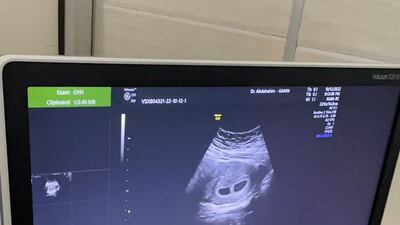

The special working group that was established in Dubai to assist Sudanese citizens called to see the couple and arranged a hospital check-up for Ms Mustafa.

She was advised that the babies would arrive earlier than expected. She was admitted to hospital where she later underwent a Caesarean section.